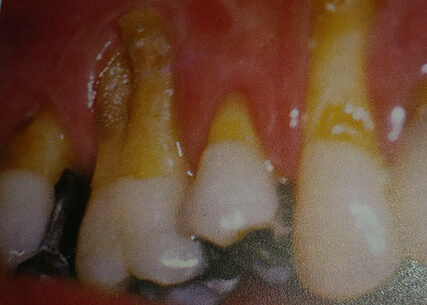

periodontal